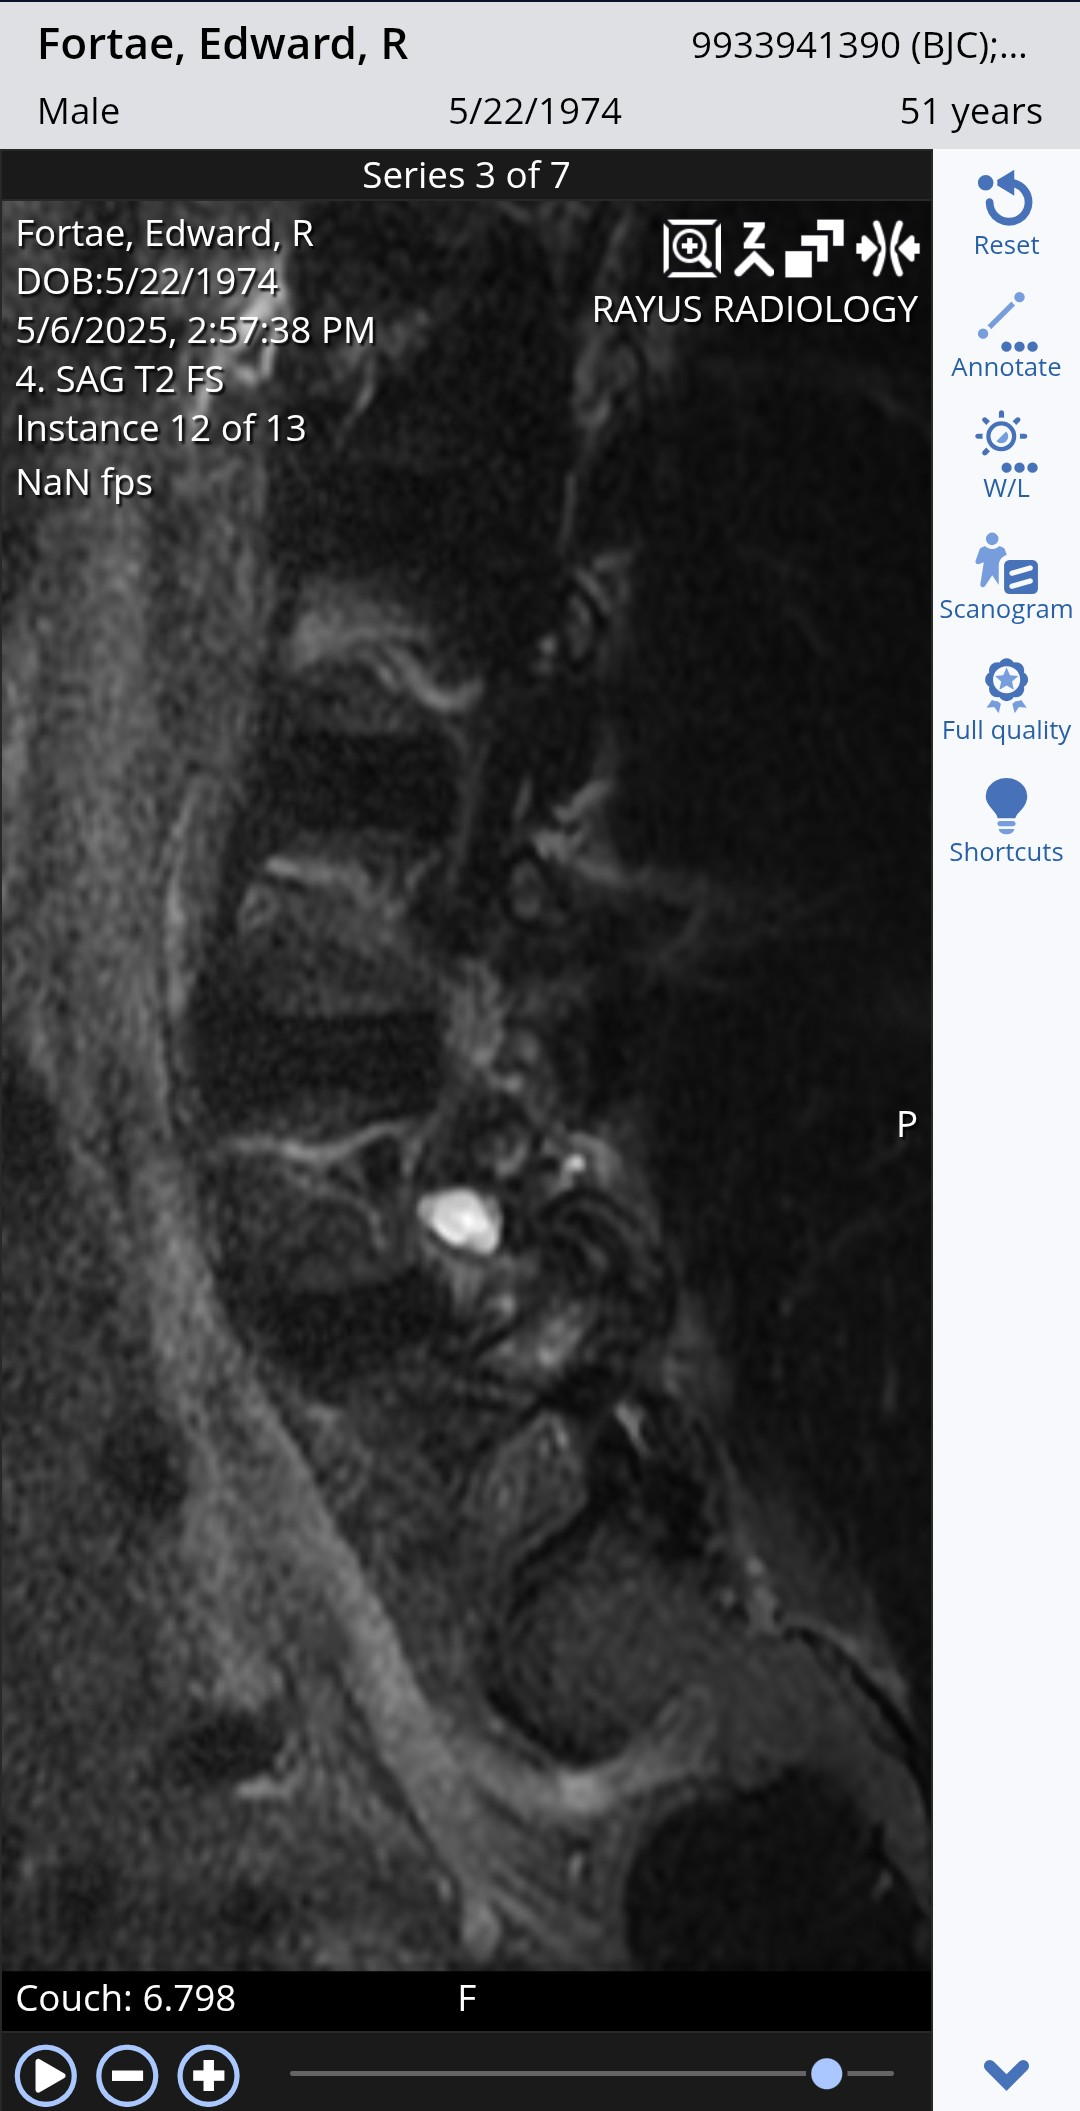

Here is the MRI of the growth from two views. As you can see it's right on the spine itself pushing on the nerves simulating a ruptured disk.

Surgery itself is relatively simple. He will cut through the back muscles and remove the growth as long as it has not grafted to the nerve root. He will remove bone to open the chamber where the root feeds the nerves to my right leg and hip.